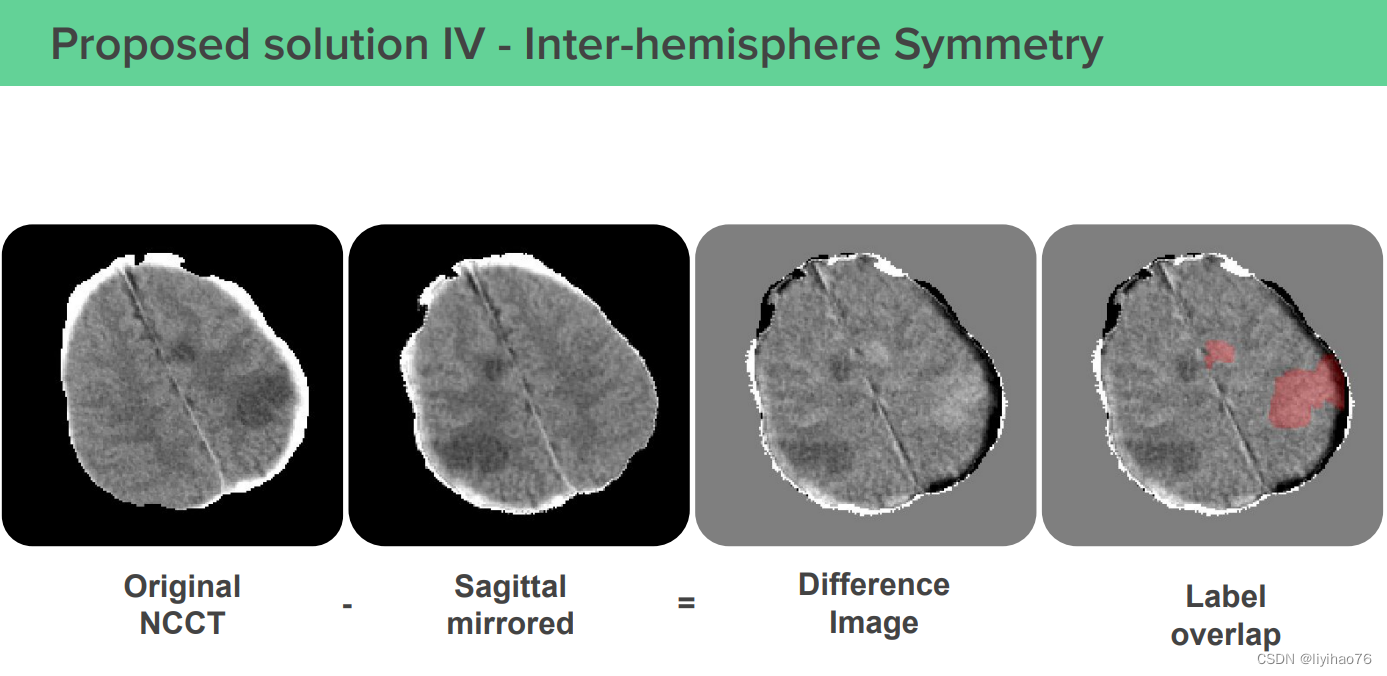

4.第一名方案 - 脑部影像人工智能公司icometrix

(2) Inter-hemisphere Symmetry